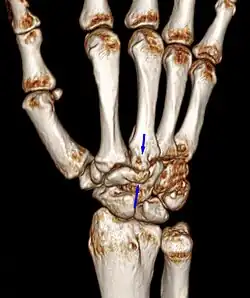

Carpal boss in plain X-Ray. -

Carpal boss in CT.